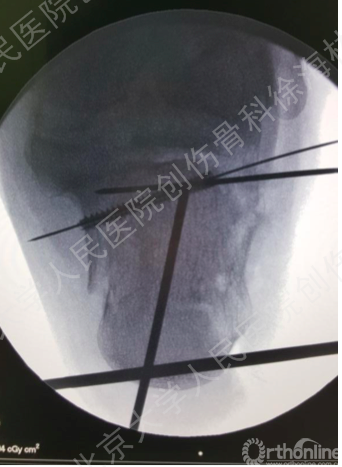

术后CT和X片

小切口+经皮钢板植入,对于跟骨骨折的微创治疗具有显著的优势。其实施的适应症和手术时机如下。

•适应证

–Sanders II型及简单的Sanders III型

–Sanders T (Int Orthop,2009): 询证医学研究中,89%的小切口治疗患者为Sanders II型、III型

•手术时机

–伤后3-5天

–等待时间过长,局部血肿机化、骨痂形成会导致复位困难